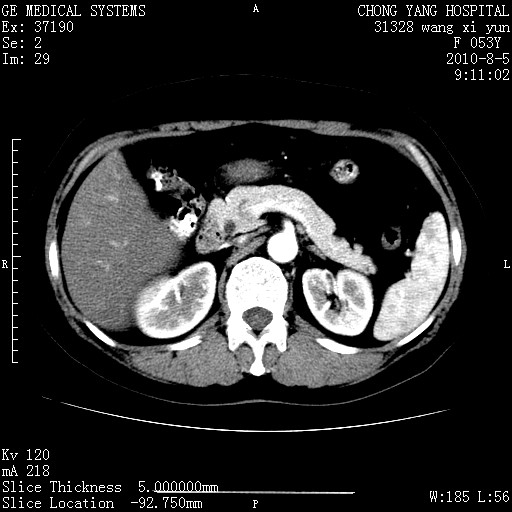

标题: CT28214:F41Y 血尿二十天,建议盆腔平扫加增强。

胆管细胞ca?

1)考虑肝左叶胆管细胞癌。2)脂肪肝。

支持胆管细胞ca。